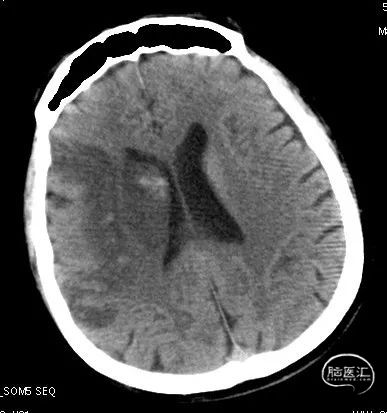

急诊颅脑CT+CTA:无脑出血,ASPECTS评分:7分;CTA示右侧M1闭塞。

急诊颅脑CT+CTA

复查24小时CT见颞叶及基底节区出血,停用并予维生素K拮抗华法林钠,至脑出血吸收后再次启动华法林钠抗凝,维持INR:1.8-2.5(心外科意见)。

术后复查CT见颞叶、基底节区出血灶